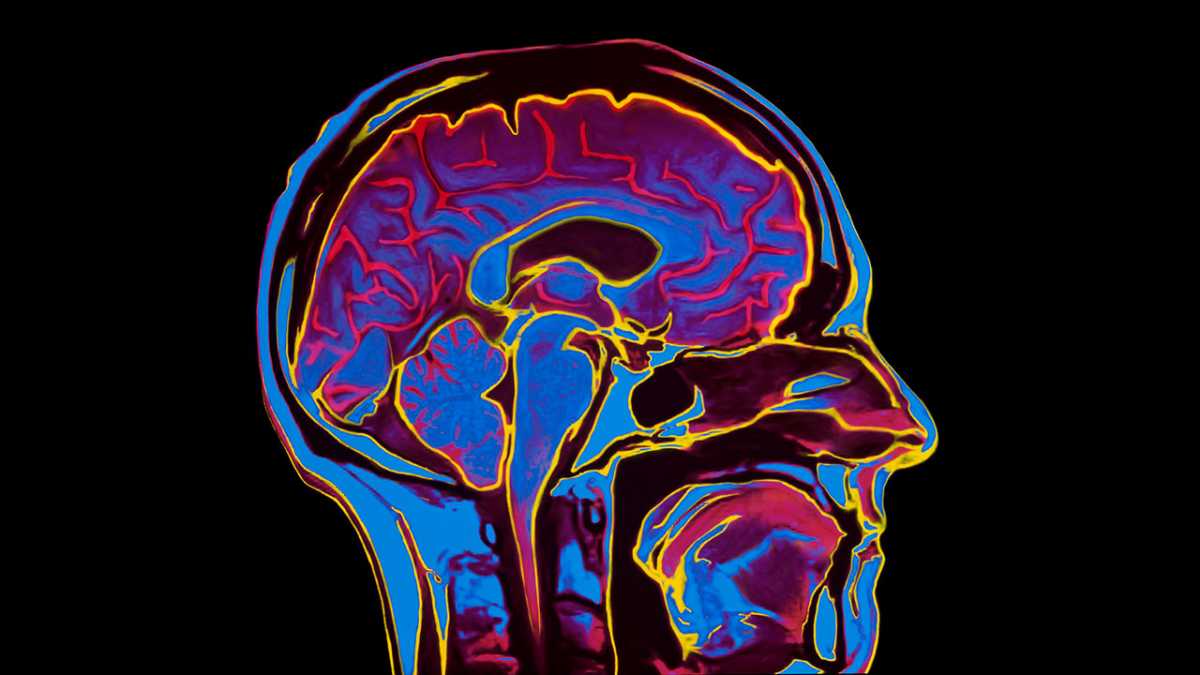

Nghiên cứu về bệnh thần kinh thường có tiến triển rất chậm, thường gắn những hy vọng sai lầm và những cuộc chiến gay go do không thể tiếp cận đầy đủ được bộ não người. Tuy nhiên, với những bước tiến gần đây trong hiểu biết về sức khoẻ tâm thần, chúng ta đã được chứng kiến nhiều hơn các khám phá về những rối loạn tâm lý phổ biến nhất, mang lại một số phát hiện hấp dẫn.

Các bệnh về não luôn là mối quan tâm hàng đầu của các nhà khoa học. Ảnh: Sciencefocus